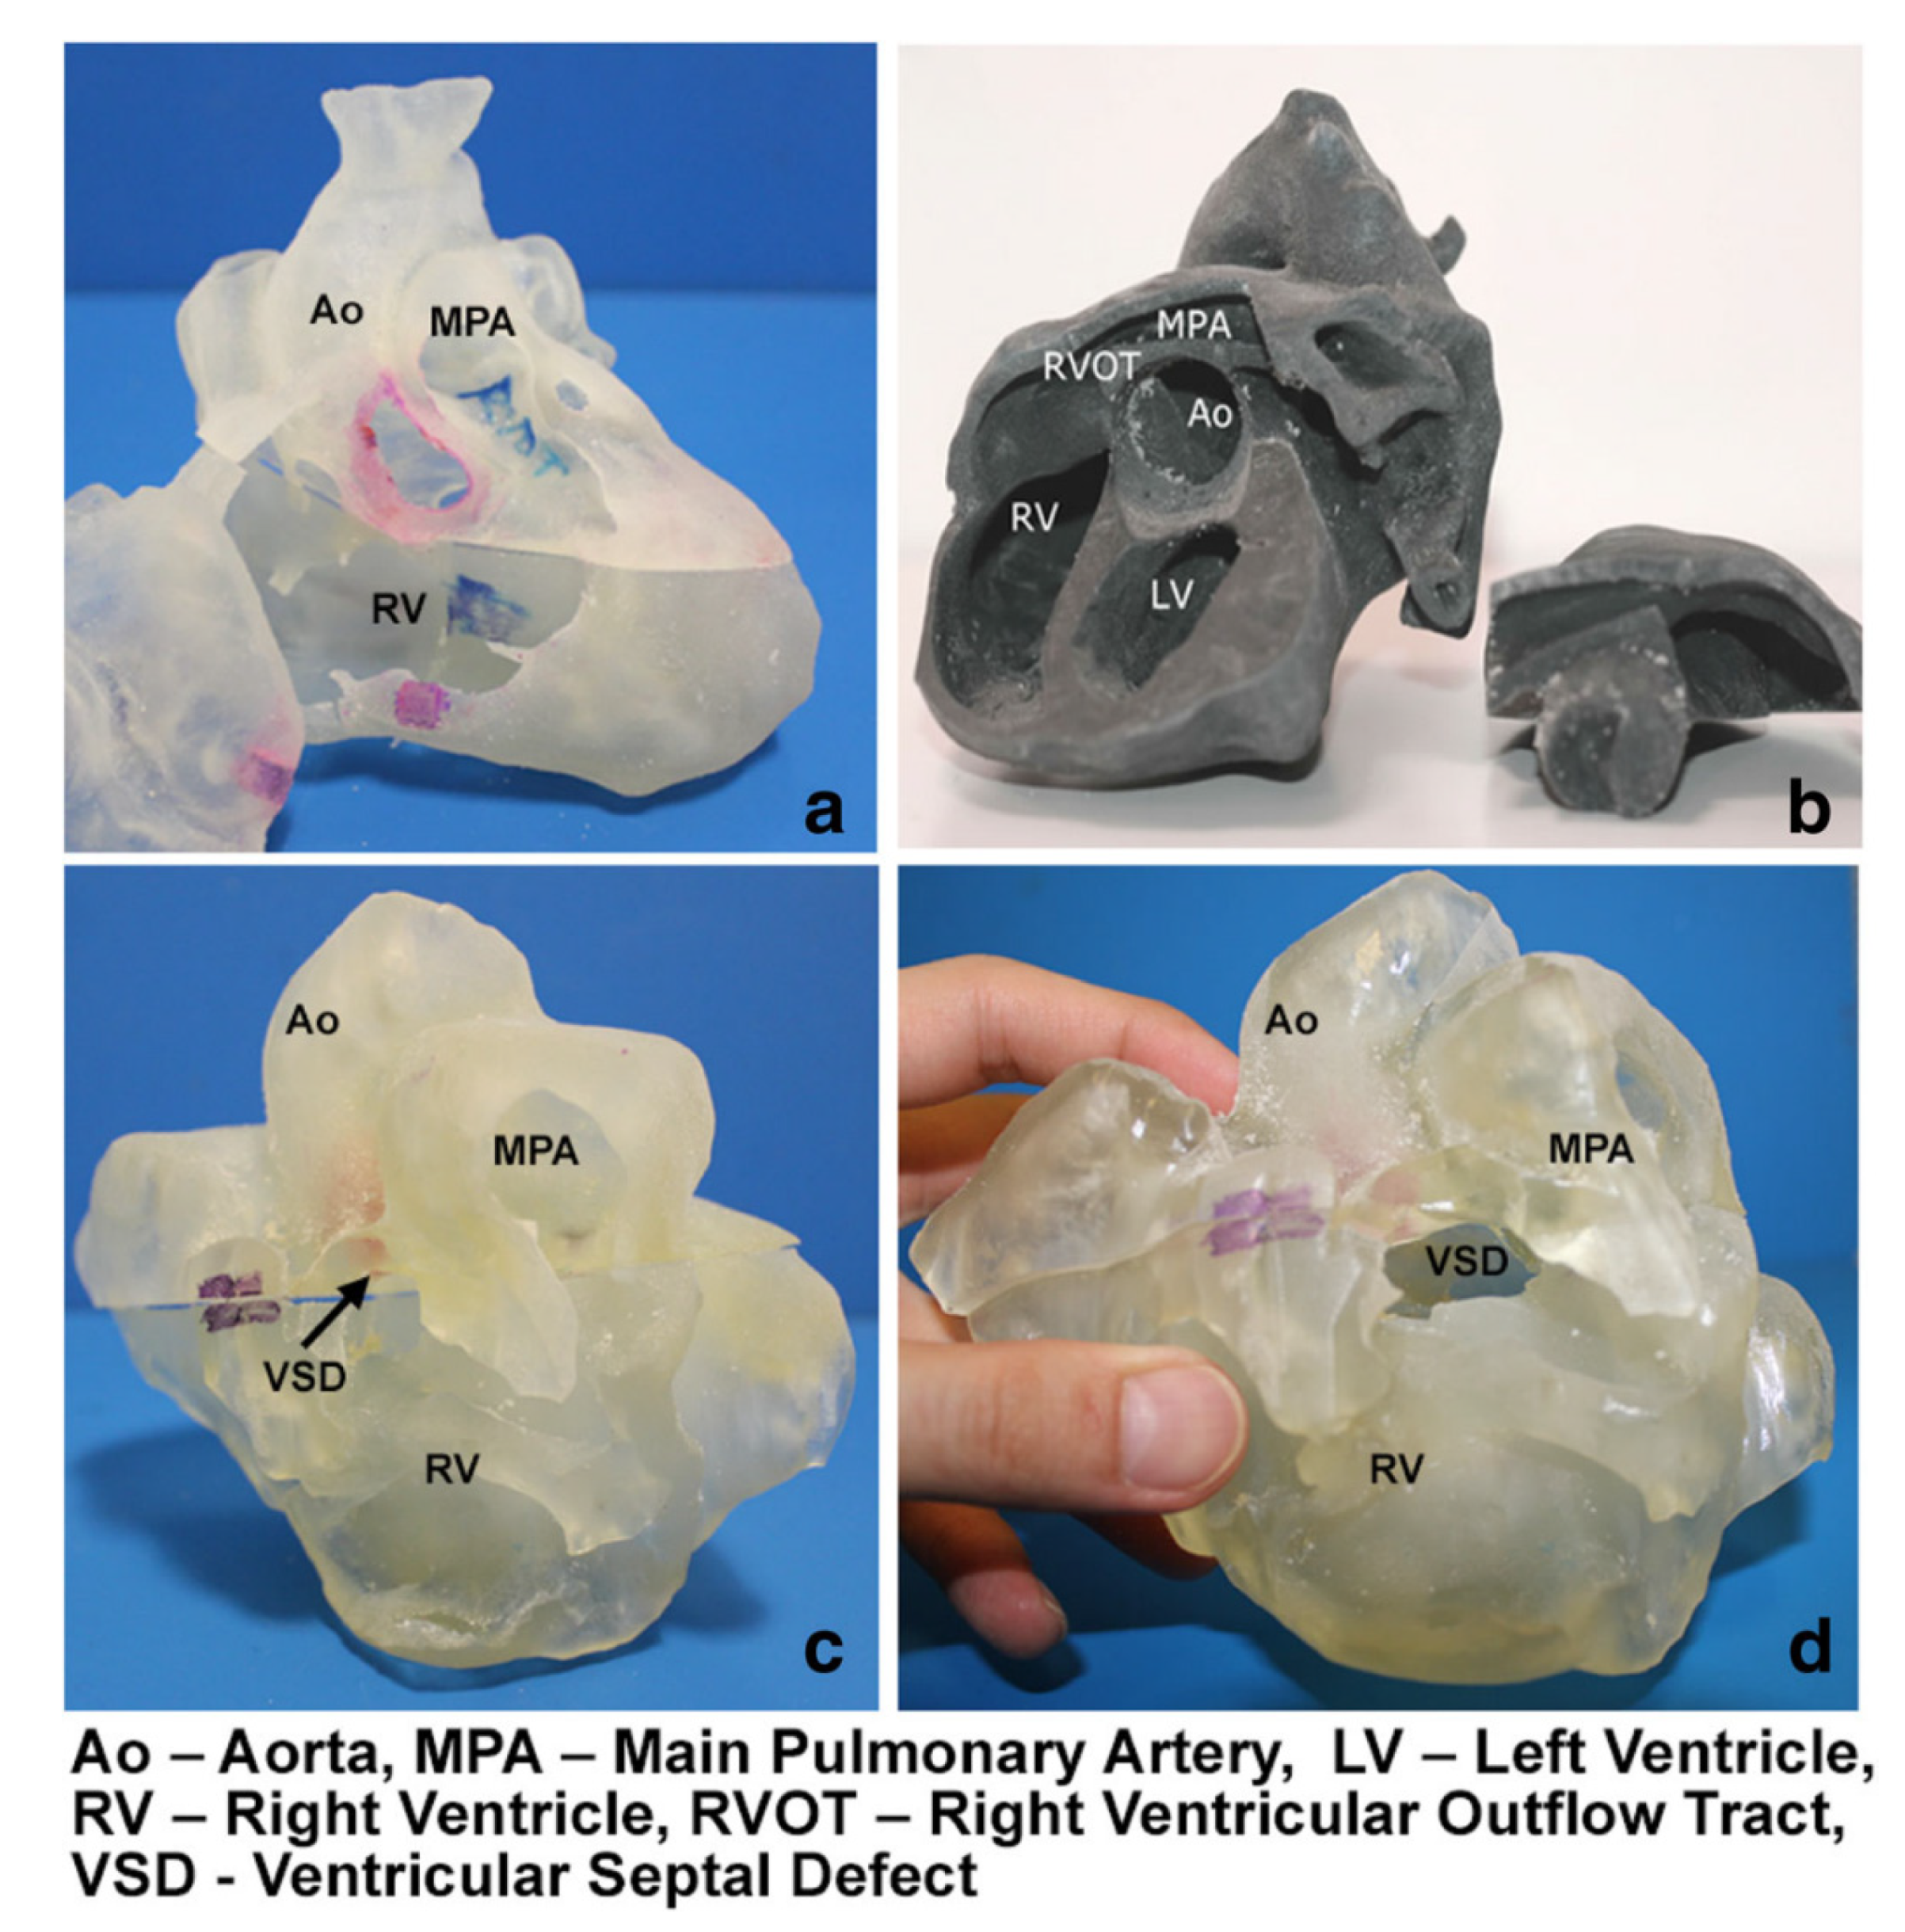

3.2. 3D Printing in Structural Heart Disease and Cardiac Interventions

- Hosny, A.; Dilley, J.D.; Kelil, T.; Mathur, M.; Dean, M.N.; Weaver, J.C.; Ripley, B. Pre-procedural fit-testing of TAVR valves using parametric modeling and 3D printing. J. Cardiovasc. Comput. Tomogr. 2019, 13, 21–30. [Google Scholar] [CrossRef]

- Tuncay, V.; van Ooijen, P.M.A. 3D printing for heart valve disease: A systematic review. Eur. Radiol. Exp. 2019, 3, 9. [Google Scholar] [CrossRef]

- Ripley, B.; Kelil, T.; Cheezum, M.K.; Goncalves, A.; Di Carli, M.F.; Rybicki, F.J.; Steigner, M.; Mitsouras, D.; Blankstein, R. 3D printing based on cardiac CT assists anatomic visualization prior to transcatheter aortic valve replacement. J. Cardiovasc. Comput. Tomor. 2016, 10, 28–36. [Google Scholar] [CrossRef]